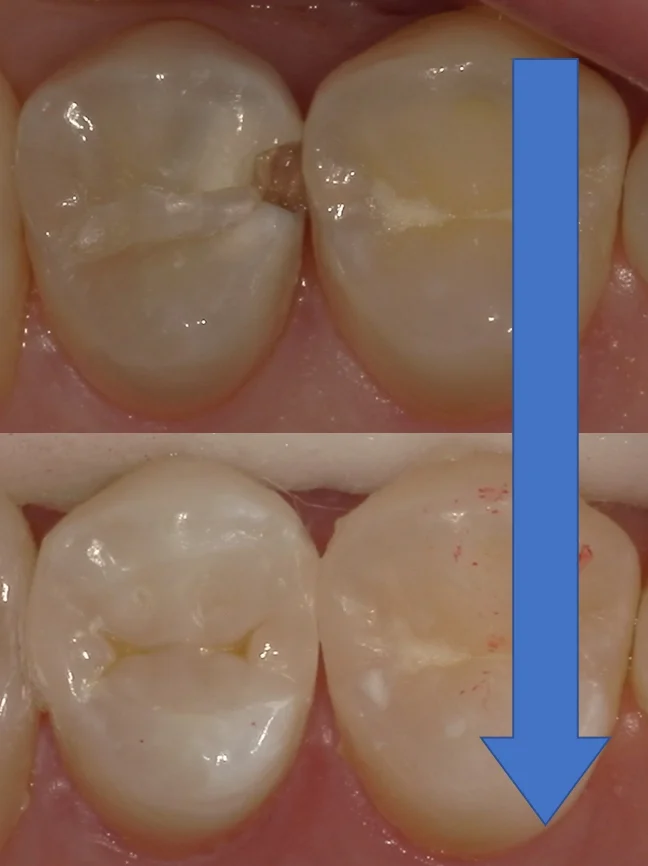

そして、詰め終わったのがこちらになります。

エナメル質が乾燥しており、白くなっているため、随分と色が合っていないように見えるかと思いますが、エナメル質に水分が戻り本来の色に戻るとこの違和感は綺麗に消えていきます。

術前術後の写真がこちらですね。

歯のカーブも、適合も問題なく行けたと思います。

術後の疼痛も無いようでホッとしました。

今後もし痛みなどが出てしまったら神経を抜くしかないですので、大事に使っていただきたいですねヽ(゚∀゚)ノ パッ☆